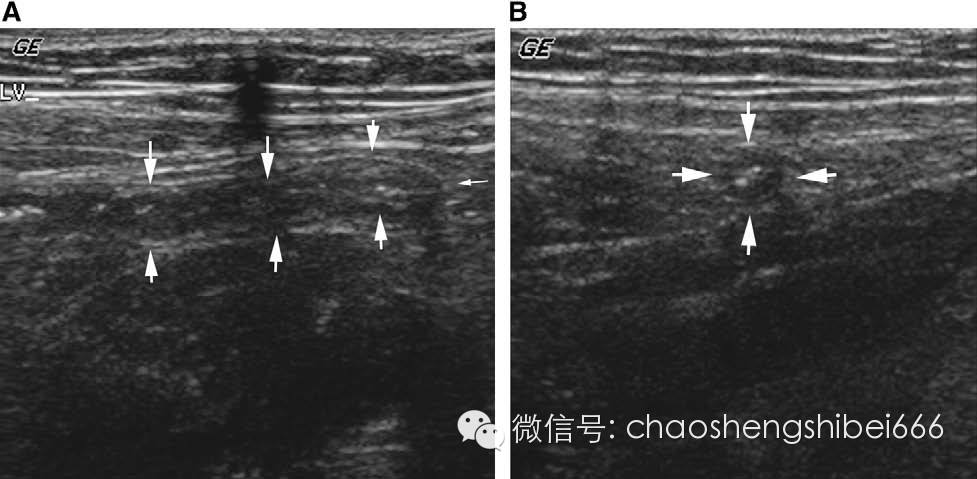

Henoch-Scho¨ nlein 紫癜(HSP)是一种特发性的血管病变。虽然病变累及全身多系统,但主要的发病还是在消化道和泌尿生殖道。虽然小儿病变主要是出现特征性的紫癜,但是消化道的受累多发生于紫癜之前。

HSP的患儿,肠壁的增厚主要是由于感染以及肠壁内出血(图11)。肠壁的异常通常是间断性的,多普勒检查可以发现血流增多,通常伴随有腹腔游离积液和肠系膜淋巴结轻度肿大,HSP的肠壁增厚可以作为肠套叠的一个诱因(图8)。如果还没有诊断HSP,出现伴随或不伴随肠套叠的肠壁增厚,应该考虑本病的诊断。

11 6岁女孩因HSP引起腹痛。A病变区肠壁明显增厚(箭头),临近可见正常肠管(B)。B 长轴图像显示另一段增厚肠管。F游离积液。C 轻度肿大的淋巴结(箭头)。